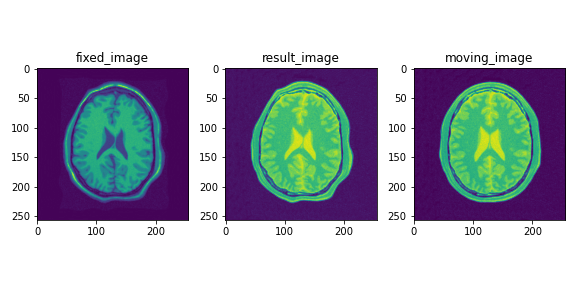

登録結果は以下のようになります.

登録前後のLocal NCC2を計算すると,各ピクセルにおいてNCCの絶対値が向上していることが確認できます.